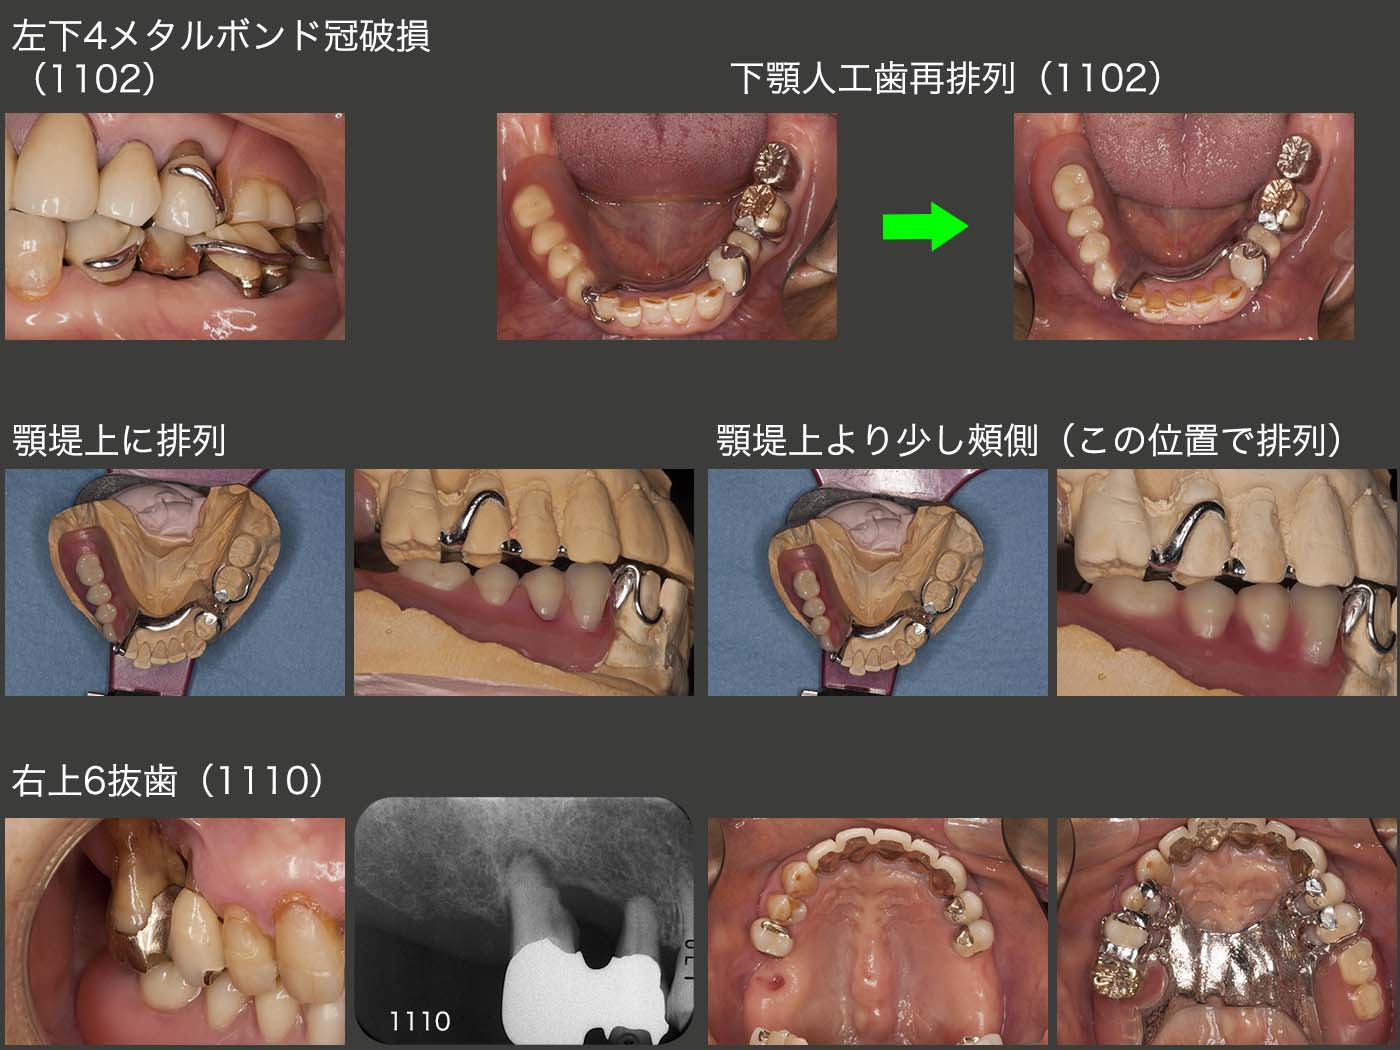

初診終了後約7年間は特に問題なく経過した.しかし,2011年2月に,まず左下4のメタルボンド冠の陶材が少し破損した.しかし,特に支障がないのでこのまま経過をみることにした.右下は犬歯以降が失われているため,どうしても咬合・咀嚼の中心は左側の咬合支持歯にならざるを得ない.したがって,左下4の存在するエリアに常に咬合力が加わるため,トラブルが生じやすい.

この状況を少しでも緩和する目的すなわち右側の義歯側でもっと咬んでもらうために,人工歯の排列位置を変更した.これまでは,上顎の天然歯としっかり咬合させて排列したため,人工歯の位置が頰側に外れていた.そこでまず顎堤上に排列したが,如何せん上顎天然歯との咬合接触面積が少なくなってしまったため,若干頰側に戻した位置を最終的な下顎の人工歯の排列位置とした.

人工歯の位置を変更したことが災いしたためか,11年10月,右上6の歯の動揺が大きくなり,このままでは連結固定してある右上5に悪影響を及ぼすため,抜歯した.装着されていた金属の冠をそのまま人工歯として再利用した.